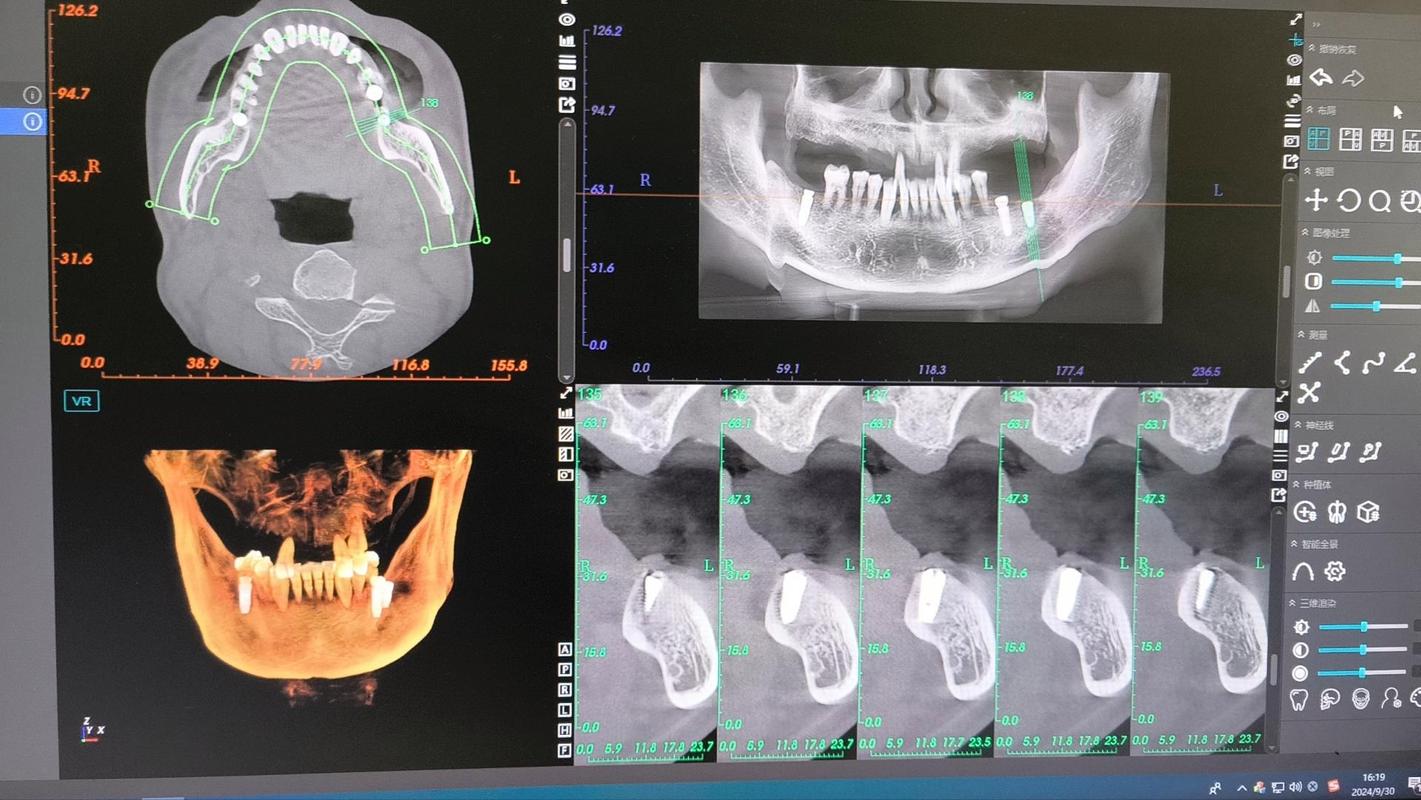

- 图像重建:扫描结束后,计算机自动将二维数据重建为三维图像(包括冠状面、矢状面、横断面及三维重建模型),医生可多角度观察。

结果解读与方案设计

CT报告通常包含以下内容,医生会结合报告制定个性化种植方案:

- 骨量评估:牙槽骨高度、宽度、厚度数据,是否达到种植标准(如下颌后牙区骨高度需≥12mm,避开下颌神经管;上颌后牙区骨高度需≥15mm,避免穿透上颌窦底)。

- 解剖结构位置:下颌神经管距离牙槽嵴顶的距离(理想≥2mm)、上颌窦底厚度(若<1mm需行上颌窦提升术)、颏孔位置(避免损伤颏神经)。

- 骨密度分级:根据CT灰度值分为D1-D4型,D1型(致密骨)需高扭矩植入,D4型(疏松骨)可能需植骨或选择表面粗糙的种植体以增强初期稳定性。

- 种植方案设计:包括种植体品牌、型号(长度、直径)、植入角度(通常与牙长轴呈15°-30°以避开邻牙牙根)、是否需植骨或使用种植导板(3D打印导板可提高植入精度0.5-1mm)。